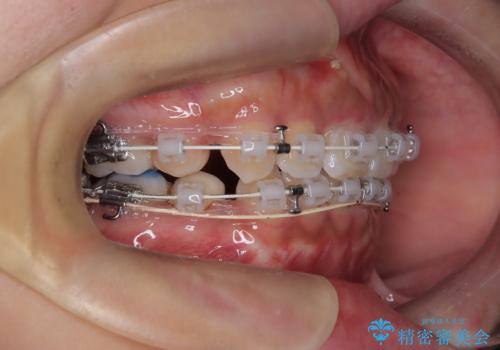

前歯の突出感を改善|上下4本の抜歯と審美ワイヤー矯正でバランスの取れた口元へ

- 患者様は、前歯の突出感を気にされて来院されました。診察の結果、歯列のスペースが不足しており、前歯を後方へ移動させるには抜歯が必要と判断。上下の小臼歯4本を抜歯し、目立ちにくい審美ワイヤー矯正(白いワイヤーと透明ブラケット)を使用して治療を行う計画を立てました。

抜歯によって前歯を下げるためのスペースを確保。その後、審美ワイヤー矯正を用いて、歯列全体のバランスを整えながら前歯を後方へ移動させました。治療後は、横顔のラインが整い、自然な口元になったことで、見た目も噛み合わせも改善しました。患者様からは「口元がすっきりして、自信を持って笑えるようになった」と喜びの声をいただきました。